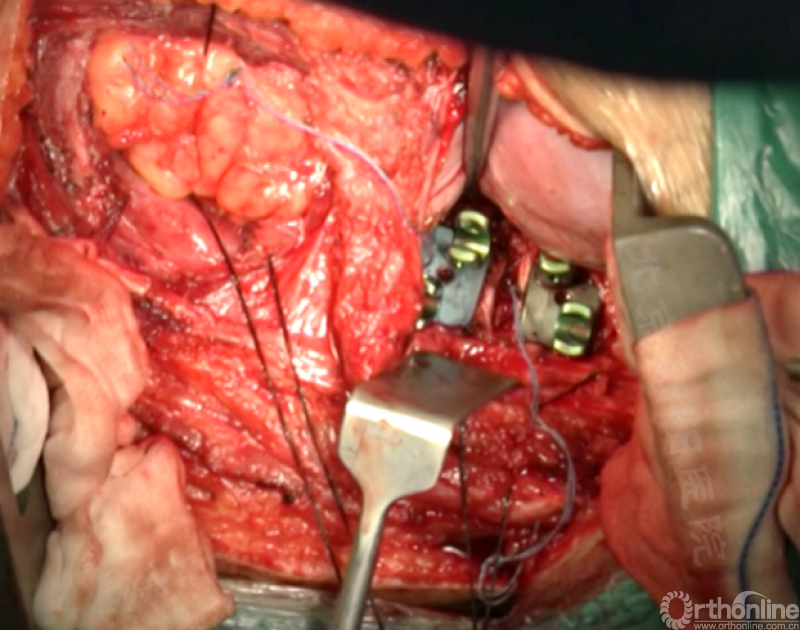

胸腔侧、腹腔侧螺钉全部置入后,骨移植物植人的越靠近后纵韧带或者纤维环的后缘越好。

将预先折弯的金属棒先置入背侧。

椎间融合器经前方置入凹侧,确保腰椎前凸的恢复和冠状面畸形的矫正,将剩下的骨移植物置入椎间隙内。

置入腹侧金属棒。

使用双棒系统时先安装背侧的棒,可进行90°的去旋转,也可以直接通过前方螺钉矫正冠状面和矢状面的畸形,然后固定后方的棒,可进一步通过加压矫正冠状面畸形。

矫正后神经检测未见异常术中唤醒患者下肢活动良好,术中透视矫正效果满意、内固定位置良好。根据手术具体情况放置合适尺寸的横连接加强内固定。

尽量多的闭合胸膜,紧密缝合横膈。